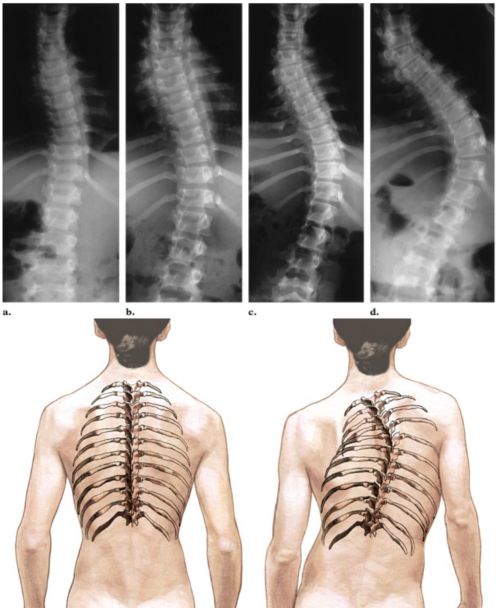

Skolyoz, omurganın göğüs (thoracic) veya bel (lumbar) bölgelerinde görülebilen, yana doğru eğriliğidir. Tek başına olabileceği gibi, kifoz (arkadan öne doğru anormal bir eğrilik) ile beraber de görülebilir (Kifoskolyoz).

Fizik muayene sırasında, hasta öne doğru eğildiğinde eğrilik daha belirgin gözükür. Farklı pozisyonlarda omurga röntgenleri ve skolyozometre (omurganın eğrilik miktarını ölçen bir alet) ölçümleri, skolyozun miktarını belirleyebilmek için yapılabilecek testlerdir.